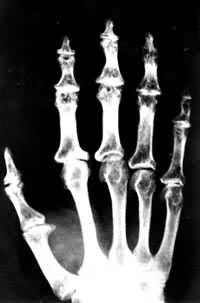

ÔçÆÚÁÙ´²±íÏÖ²¢²»Ã÷ÏÔ¡£µ±²¡Çé·¢Õ¹µ½Ö±½ÓÓ°Ï컼¶ù»î¶¯Ê±£¬XÉäÏßËù¼ûÒѺÜÑÏÖØ¡£ÌÛÍ´¶àÊý°éÓÐÊÖָĩ½ÚÍäÇú¡¢ ÊÖÖ¸Íáб£¨Í¼1£©¡£ÌÛÍ´³£Îª¶à¹Ø½Ú¡¢¶à·¢¡¢¶Ô³Æ»ò·Ç¶Ô³ÆÐÔ£¬Ö¢×´¶à·¢ÉúÓÚÊÖºÍõ׹ؽڡ£Óеϼ¶ùÖ»ÓÐÊÖ²¿µÄ±íÏÖ£¬ÊÖָĩ½ÚÍäÇú£¬¹Ø½ÚÖ×´ó¡£ÓеÄ÷ŹؽںÍõ׹ؽÚÌåÕ÷Ã÷ÏÔ£¬¶øÊÖ²¿È´ÎÞÃ÷ÏÔÒì³£¡£»¹ÓеϼÕß÷ŹؽÚÇüÇúÂÎËõ£¬ëŹDZä¶Ì£¬¹Ø½ÚÔö´ó£¬ÉíÌ尫С£¬²½Ì¬ÈçѼ²½¡£ÖØÖ¢»¼¶ùÓÐÆ½×㣬×ãÖ۹ǽá½Ú¡͹£¬×ã¸úÍâ·­£¬¸ú¹Ç½á½Ú±ä¶Ì£¬ÐÐ×ßʱ¹³²»×¡Ð¬£¬ÉõÖÁ½µµÍ»òɥʧÀͶ¯ÄÜÁ¦¡£

´ó¹Ç½Ú²¡µÄÊÖ½Å

ÊǶùͯ·¢ÓýÆÚ´ó¹Ç½Ú²¡ÍíÆÚÐÞ¸´µÄºóÒÅ»ûÐΣ­¹Ç¹Ø½Ú²¡¡£È«Éí¸÷²¿Î»¶¼¿É·¢Éú£¬ÐÎ³É¶à¹Ø½ÚÔöÉú¸Ä±ä¡£ÁÙ´²ºÍXÉäÏßµÄÍ»³ö±íÏÖΪ¹Ç½ÚÔö´ó£¬×µÌå¡¢¹ÇÅèºÍËÄÖ«´ó¹Ø½ÚµÄ¹Ç¶ËÒà¿É·¢Éú¹ÇÖÊȱË𡢹ǸÉËõ¶Ì¡¢¹Ø½Ú±äÐÎ £¨Í¼2£©¡£

³ÉÈË´ó¹Ç½Ú²¡ÊÖ²¿¸÷¹Ø½ÚÔö´ó±äÐΣ¬Îª¶ùͯÆÚÈí¹Ç»µËÀºóÒÅÁôµÄ¹Ø½Ú»ûÐÎ